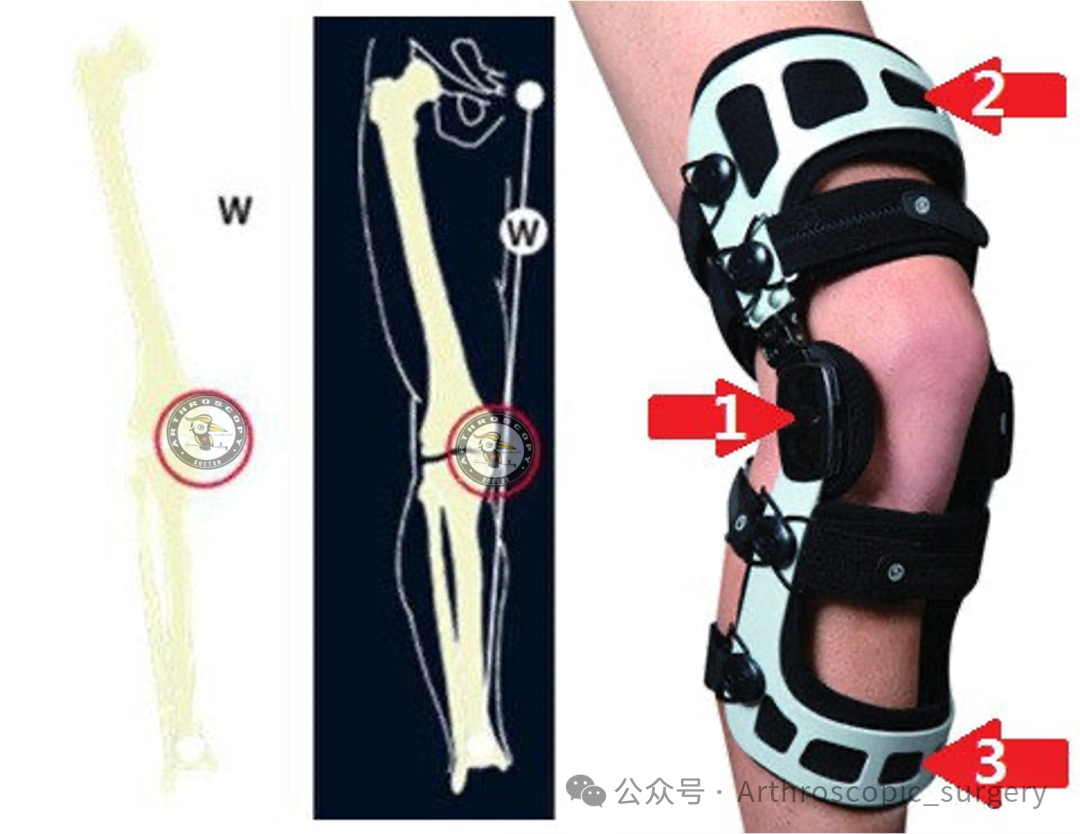

对于存在膝关节内翻畸形的患者,佩戴内侧间室免荷支具有助于缓解症状。

若下肢全长X线片(HKA片)显示负重轴位于胫骨内侧髁间嵴内侧(或内翻畸形>5°),应考虑同期进行截骨矫形手术。

推荐意见 55:

对于年轻活跃患者(<50岁),若参与高冲击活动且存在显著膝关节内翻畸形(>5°),修复MMRT时可考虑同期进行截骨矫形手术。

推荐意见 56:

对于老年活跃患者(>50岁),若参与高冲击活动且存在显著膝关节内翻畸形(>5°)合并轻度骨关节炎,修复MMRT时可考虑同期进行截骨矫形手术。

对于未行外翻截骨矫形的内翻畸形患者,术后可考虑使用内侧间室免荷支具。

推荐意见 69:

术后初期负重阶段可考虑使用膝关节支具(如免荷支具),尤其适用于接受半月板中央化或其他附加手术的患者。